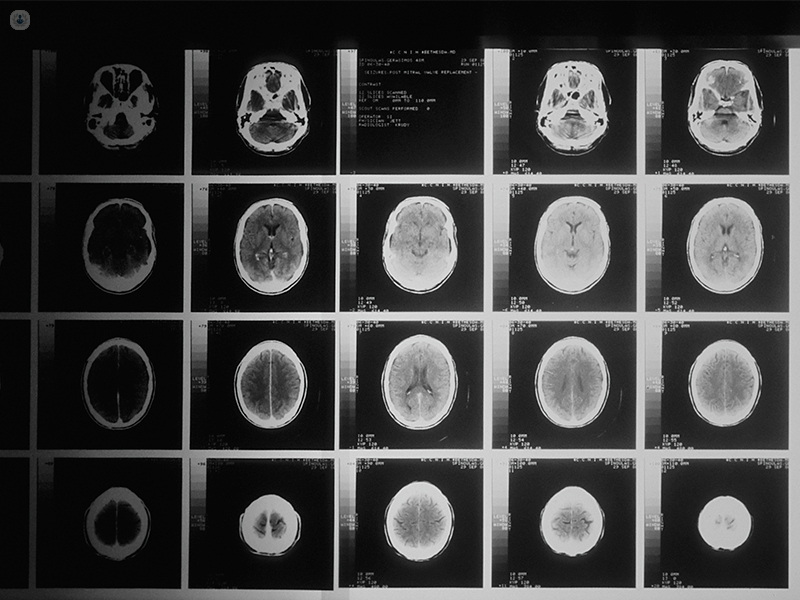

La LITT si si differenzia dalle cure neurochirurgiche tradizionali per la modalità di rimozione del tumore e la mini-invasività. Infatti, essa consiste in una termoablazione (ossia resezione/riduzione del tumore mediante calore) ottenuta usando il laser come fonte di calore per danneggiare il tumore. Il trattamento consiste nell’inserire nel cranio del paziente una sonda contenente una fibra ottica che viene posizionata all’interno del tumore il quale viene progressivamente distrutto dal calore rilasciato dalla fibra stessa, senza danno per il cervello circostante. La sonda viene posizionata con notevole precisione utilizzando sistemi di navigazione robotica che, oltre alla accuratezza, garantiscono la possibilità di utilizzare solo una piccola incisione sul cuoio capelluto e un piccolo foro nel cranio per effettuare l’intera procedura. Quest’ultima viene eseguita con un monitoraggio continuo tramite risonanza magnetica.

Nata per le cure dei tumori del fegato e della tiroide, la LITT è ora usata anche per altri tumori come quelli della prostata e del cervello. Le neoplasie cerebrali trattate con la LITT sono generalmente tumori localizzati in aree difficili da raggiungere chirurgicamente e/o di dimensioni non molto cospicue. Gliomi e metastasi cerebrali sono i tumori più frequentemente trattati negli adulti. Nei bambini, si tratta spesso di forme tumorali particolari, come l’amartoma dell’ipotalamo (spesso causa di epilessia), l’astrocitoma subependimale a cellule giganti (o SEGA, comune nella sclerosi tuberosa) o altri tipi di astrocitomi. Lo spettro di tumori trattati è in aumento.

La LITT agisce necrotizzando il tumore cerebrale: il calore rilasciato nel tumore “uccide” progressivamente le sue cellule senza bisogno che il tessuto tumorale venga rimosso. Il danno alle cellule tumorali avviene distruggendo le membrane protettive e i piccoli organi in esse contenuti o alterandone il DNA (il che impedisce alla cellula di proliferare).